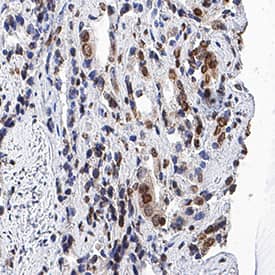

IkB-a antibody in Human Prostate Cancer Tissue by Immunohistochemistry (IHC-P).

IkB‑ alpha in Human Prostate Cancer Tissue.

IkB-a was detected in immersion fixed paraffin-embedded sections of human prostate cancer tissue using Mouse Anti-Human IkB-a Monoclonal Antibody (Catalog # MAB4299) at 5 µg/mL for 1 hour at room temperature followed by incubation with the Anti-Mouse IgG VisUCyte™ HRP Polymer Antibody (Catalog # VC001). Tissue was stained using DAB (brown) and counterstained with hematoxylin (blue). Specific staining was localized to cytoplasm and nuclei in cancer cells. View our protocol for IHC Staining with VisUCyte HRP Polymer Detection Reagents.